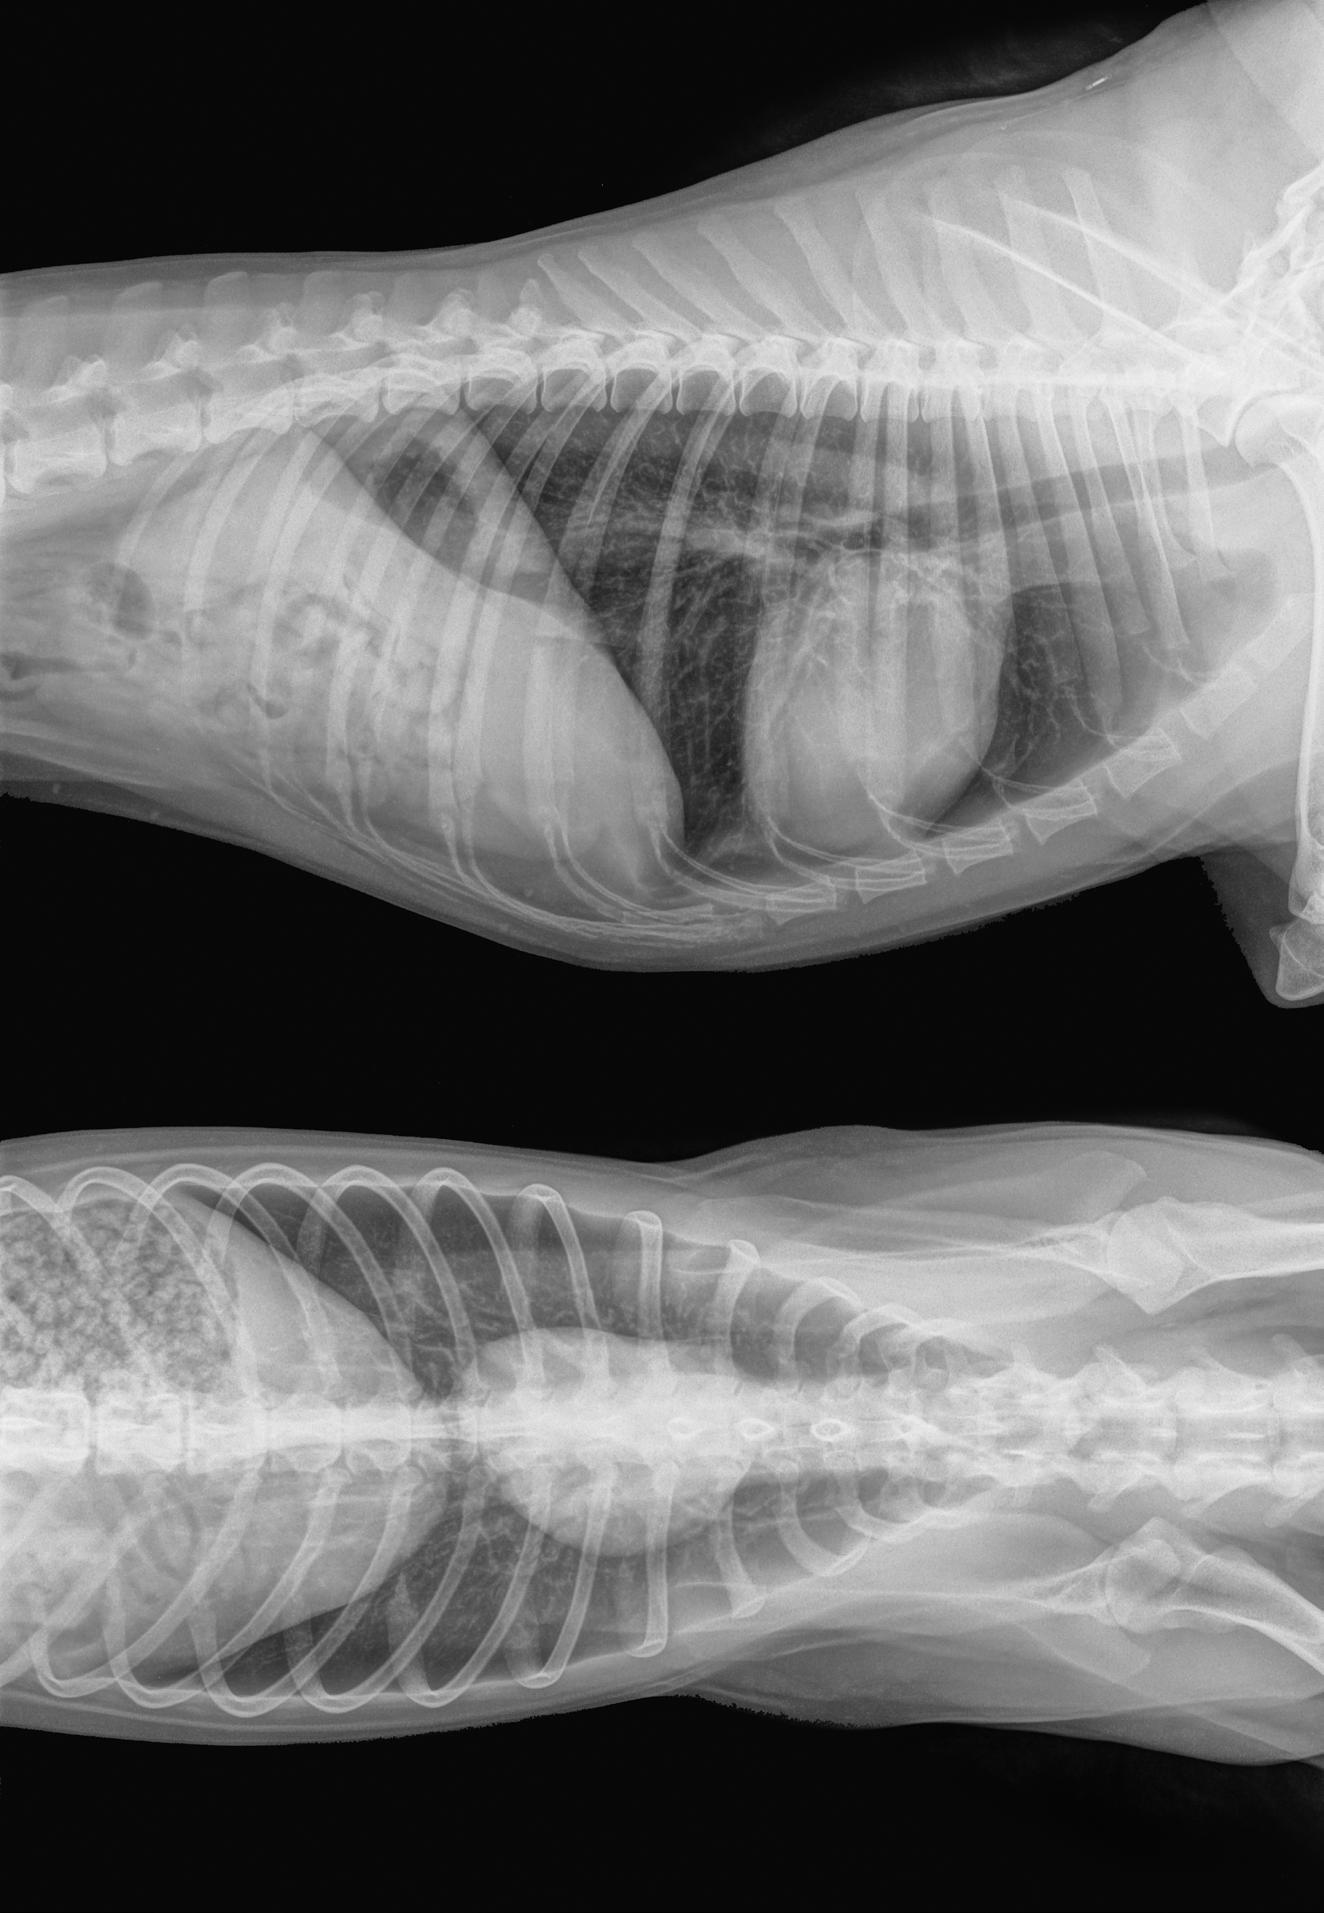

• Echocardiography (ultrasound of the heart): To evaluate

valve function, heart size, and regurgitation severity.

• Chest X-rays: To check for heart enlargement or fluid in the lungs.